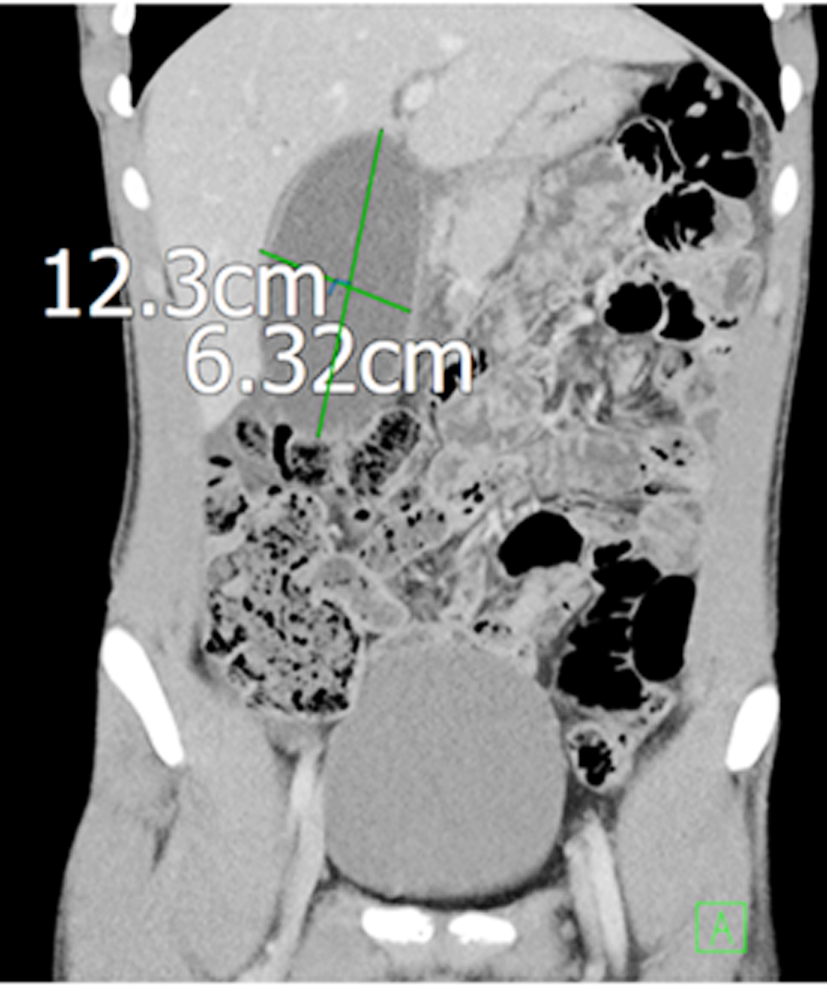

In September 2023 he returned with recurrent pain in right hypochondriac region associated with vomiting. On clinical examination he was tender in right hypochondriac region. He was evaluated with blood tests and imaging. His inflammatory markers were raised (WBC count and CRP). The contrast enhanced CT scan abdomen and pelvis revealed pericholecystic fluid and hugely distended gallbladder causing compression over the pylorus/duodenum thus causing mechanical gastric outlet obstruction (fig. 4). MRCP scan also reconfirmed the findings (fig. 5) and did not show any stones or strictures anywhere in the biliary tract.

Figure 4 - The contrast enhanced CT scan abdomen and pelvis revealed pericholecystic fluid and hugely distended gallbladder causing compression over the pylorus/duodenum thus causing mechanical gastric outlet obstruction